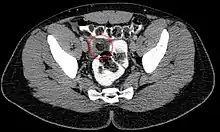

Epiploic appendagitis in computed tomography.

Abdominal CT scan, Epiploic Appendagitis (circle)